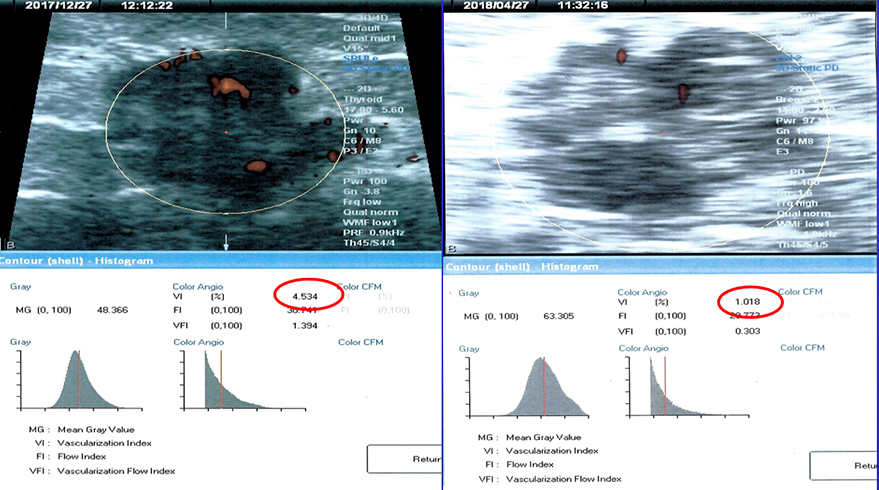

Rx Success-Breast Cancer 12/17 vi=4.5% 4/18 vi=1.0%

Once you have a vascular map of the cancer, we have the initial vessel density of 4.5%. Successful treatment over weeks or months will bring it down. In this case, it's down to one quarter of the initial treatment so this is treatment success. This is quantitative mapping of treatment follow-up because if it's working, it's better to change treatment, to avoid the side effects of chemo or other immunotherapies.

The first circle on top shows the red tumor vessels. The 4D Instagram computer reconstruction gives you a quantitative measure of how many tumor vessels are present. Once you have a number, you can follow the number up or down to verify treatment success or failure to adequately adjust treatment that's needed up or down.